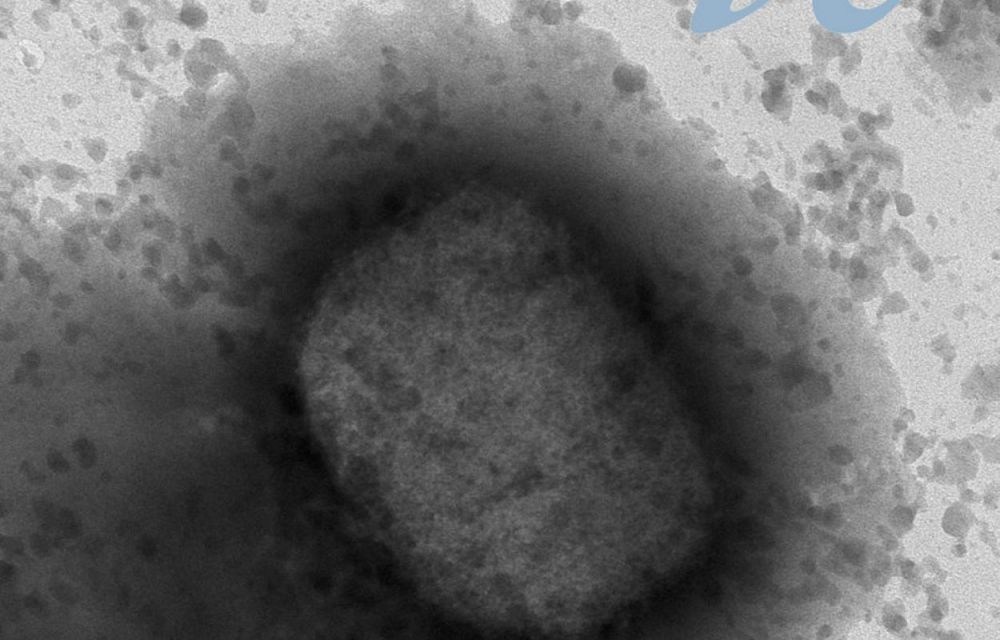

És una malaltia que pot acabar afectant els animals domèstics de companyia més habituals, en particular els gats, que solen infectar-se quan entren en contacte amb altres animals portadors (rosegadors) i que poden acabar actuant com a reservori natural del virus i, per tant, esdevenir un focus de propagació del virus cap a les persones o cap a altres animals. Els animals infectats poden presentar lesions a la pell, que comencen a la zona del cap i s’estenen a la resta del cos, especialment a les potes i les orelles.